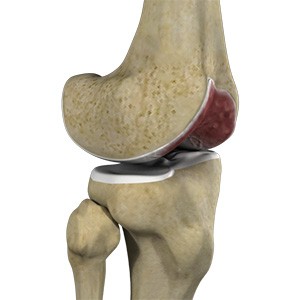

Osteochondral Defect of the Knee

An osteochondral defect, also commonly known as osteochondritis dissecans, of the knee refers to a damage or injury to the smooth articular cartilage surrounding the knee joint and the bone underneath the cartilage. The degree of damage may range from a rupture of the cartilage to a slight crack of the bone to a piece of the bone breaking off within the joint.